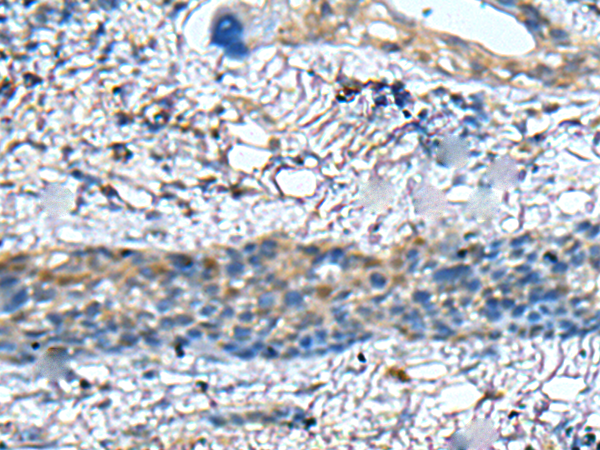

(The image on the left is immunohistochemistry of paraffin-embedded Human colorectal cancer tissue using ZNF512 Antibody at dilution 1/30, on the right is treated with fusion protein. (Original magnification: x200))